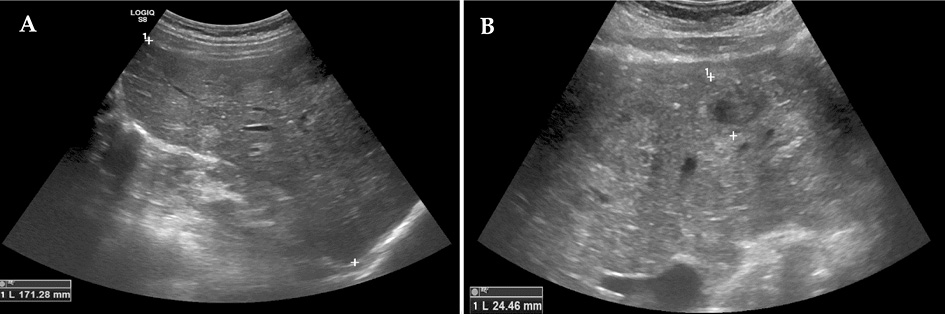

Metastatic foci were confirmed by performing a full-body computed tomography (CT) scan, which showed hepatomegaly (right lobe ~184 mm), multiple hypodense solid diffusely distributed masses in the liver (to 3 cm in diameter), spleen (to 3.7 cm in diameter), and kidneys (to 12 mm in diameter), moderate interstitial, para-aortic, paratracheal, and aortocaval lymphadenopathy, and disc atelectasis in the lungs (Figure 2, A–C).

Figure 2. Computed tomography images. Multiple hypodense solid diffusely distributed masses (arrows) in the liver (A–C), spleen (B) and kidneys (C); disc atelectasis in the right lung (arrow) (A).